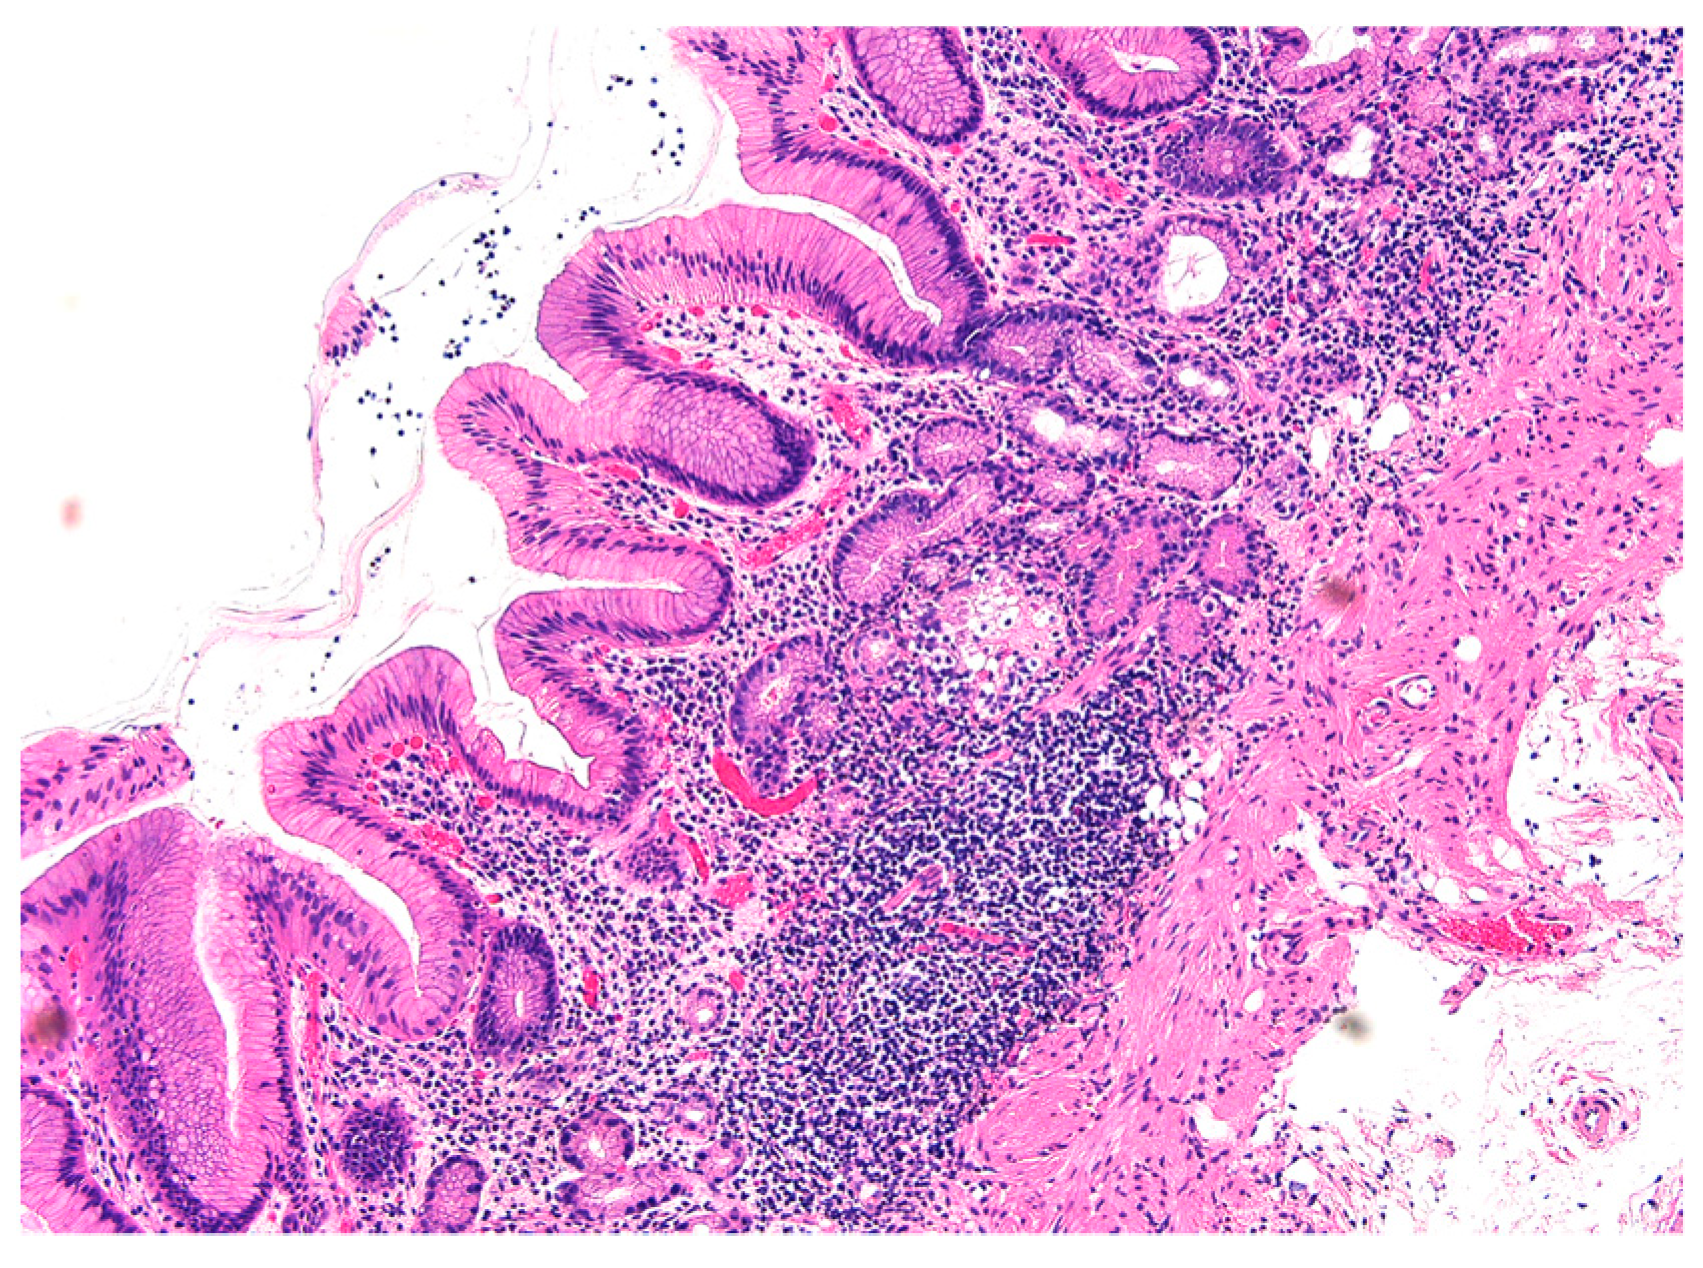

4.1. Histopathological Findings

4.2. Endoscopic Findings